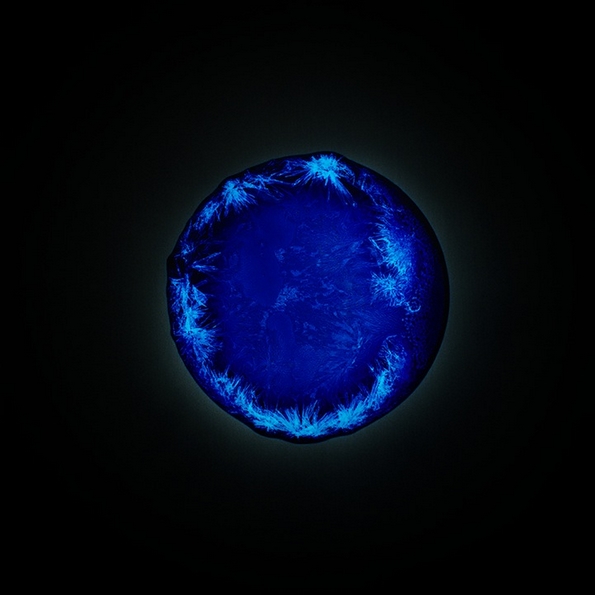

Екстази

Па така, решила да го спроведе овој проект и успеала да направи одлични фотографии. Таа капнала по неколку капки од различни илегални и легални дроги на филм за апарат кој претходно бил осветлен. Во реакција со филмот, супстанците се зголемиле и рашириле во аморфни форми и живописни бои, што резултирало со одлични фотографии. Таа ја нарекла серијата фотографии „All You Can Feel“.